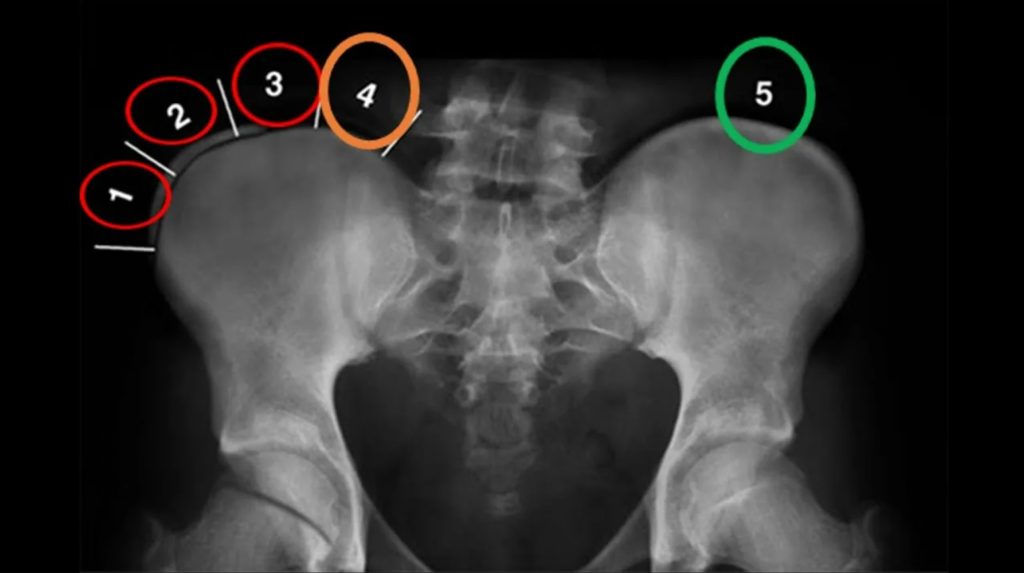

Шкала Риссера — радиографическая система стадирования скелетной зрелости по степени окостенения и последующего сращения апофиза гребня с подвздошной костью на рентгенограмме таза/поясничного отдела.[6][1]

Классическая (Риссер 0–5) схема (евро‑американский вариант):[1][6]

| Риссер 0 | Отсутствие оссификации апофиза гребня подвздошной кости. Максимальный потенциал роста впереди или в разгаре (особенно при препубертатном скачке роста). |

| Риссер 1 | Оссификация апофиза начинается в области передней верхней ости, занимает примерно 25% дуги подвздошного гребня. Потенциал роста ещё значителен, высокий риск прогрессирования при идиопатическом сколиозе. |

| Риссер 2 | Оссифицировано примерно 25–50% апофиза. Рост замедляется, но остаётся существенным; у пациентов с углом Кобба ≥25° сохраняется показание к активной корсетотерапии и сколиоз‑специфическим упражнениям (Schroth, SEAS, др.).[4] |

| Риссер 3 | Оссификация 50–75% подвздошного гребня. Потенциал роста снижается, но полностью не исчерпан. |

| Риссер 4 | Оссификация 100% апофиза, но без полного сращения с подвздошной костью. Скелет близок к зрелости, рост в длину минимален, но риск позднего прогрессирования всё ещё существует.[3][1] |

| Риссер 5 | Полное сращение апофиза с подвздошной костью. Считается наступлением скелетной зрелости, дальнейший рост в длину практически отсутствует.[6][1] |